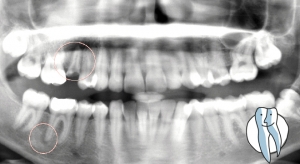

Ein Zahn leidet unter einer tiefen Karies, der empfindliche Nerv wird so stark gereizt, dass er sich entzündet. Diese Entzündung breitet sich bis in den umliegenden Knochen aus, mit der Folge, dass auch ausserhalb des Zahnes Nerven und Blutgefässe erst entzünden, dann absterben. In der Folge wird der Zahn von innen nicht mehr durchblutet, somit nicht mehr ernährt, das Immunsystem des Zahnes ist nur noch stark vermindert wirksam. Der Zahn wird dunkel und spröde, eine Füllung ist nur noch schwer dauerhaft zu verkleben. In den meisten Fällen raten wir zu einer Wurzelkanalbehandlung mit anschliessender Überkronung.